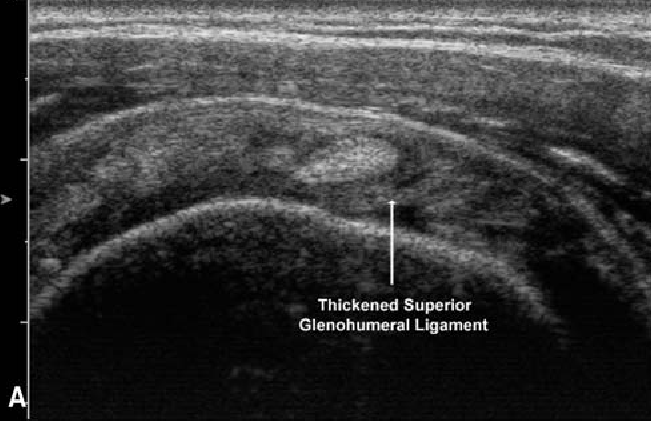

초음파상

비대된 인대가 관찰되고,

도플러 신호가 활성화되었으며,

관절낭이 부어있다면

도침치료**가 아주 효과적입니다.